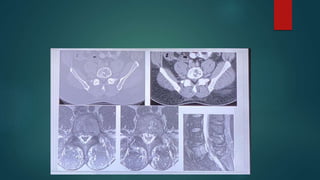

Renal important spotter

Ectopic kidney and pancake kidney

Horseshoe kidney